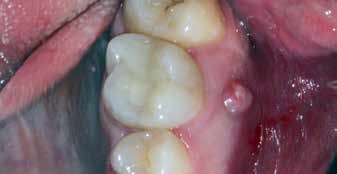

Als sich der Patient immer noch schmerzfrei 4 Wochen später im Rahmen des Termins zur definitiven Versorgung in der Praxis vorstellte, war lediglich noch das Fistelmaul, aber keine Erhebung am Zahnfleisch mehr zu sehen (Abb. 4). Nachdem auch sonst keine Auffälligkeiten festzustellen waren, wurde wie geplant mit der endgültigen Versorgung des Zahnes 26 begonnen. Hierfür wurde zunächst eine Isolierung des Zahnes mit Kofferdam vorgenommen (Abb. 5). Für ein genaueres Bild vom Verlauf der Wurzelkanalanatomie lieferte eine Kontrastaufnahme mithilfe von K-Feilen und eines Silberstiftes, mb2, (Abb. 6) die notwendigen Informationen. Dabei stellte sich heraus, dass insbesondere einer der Kanäle sich durch eine außerordentliche Krümmung von beinahe 90° auszeichnete (Abb. 7).